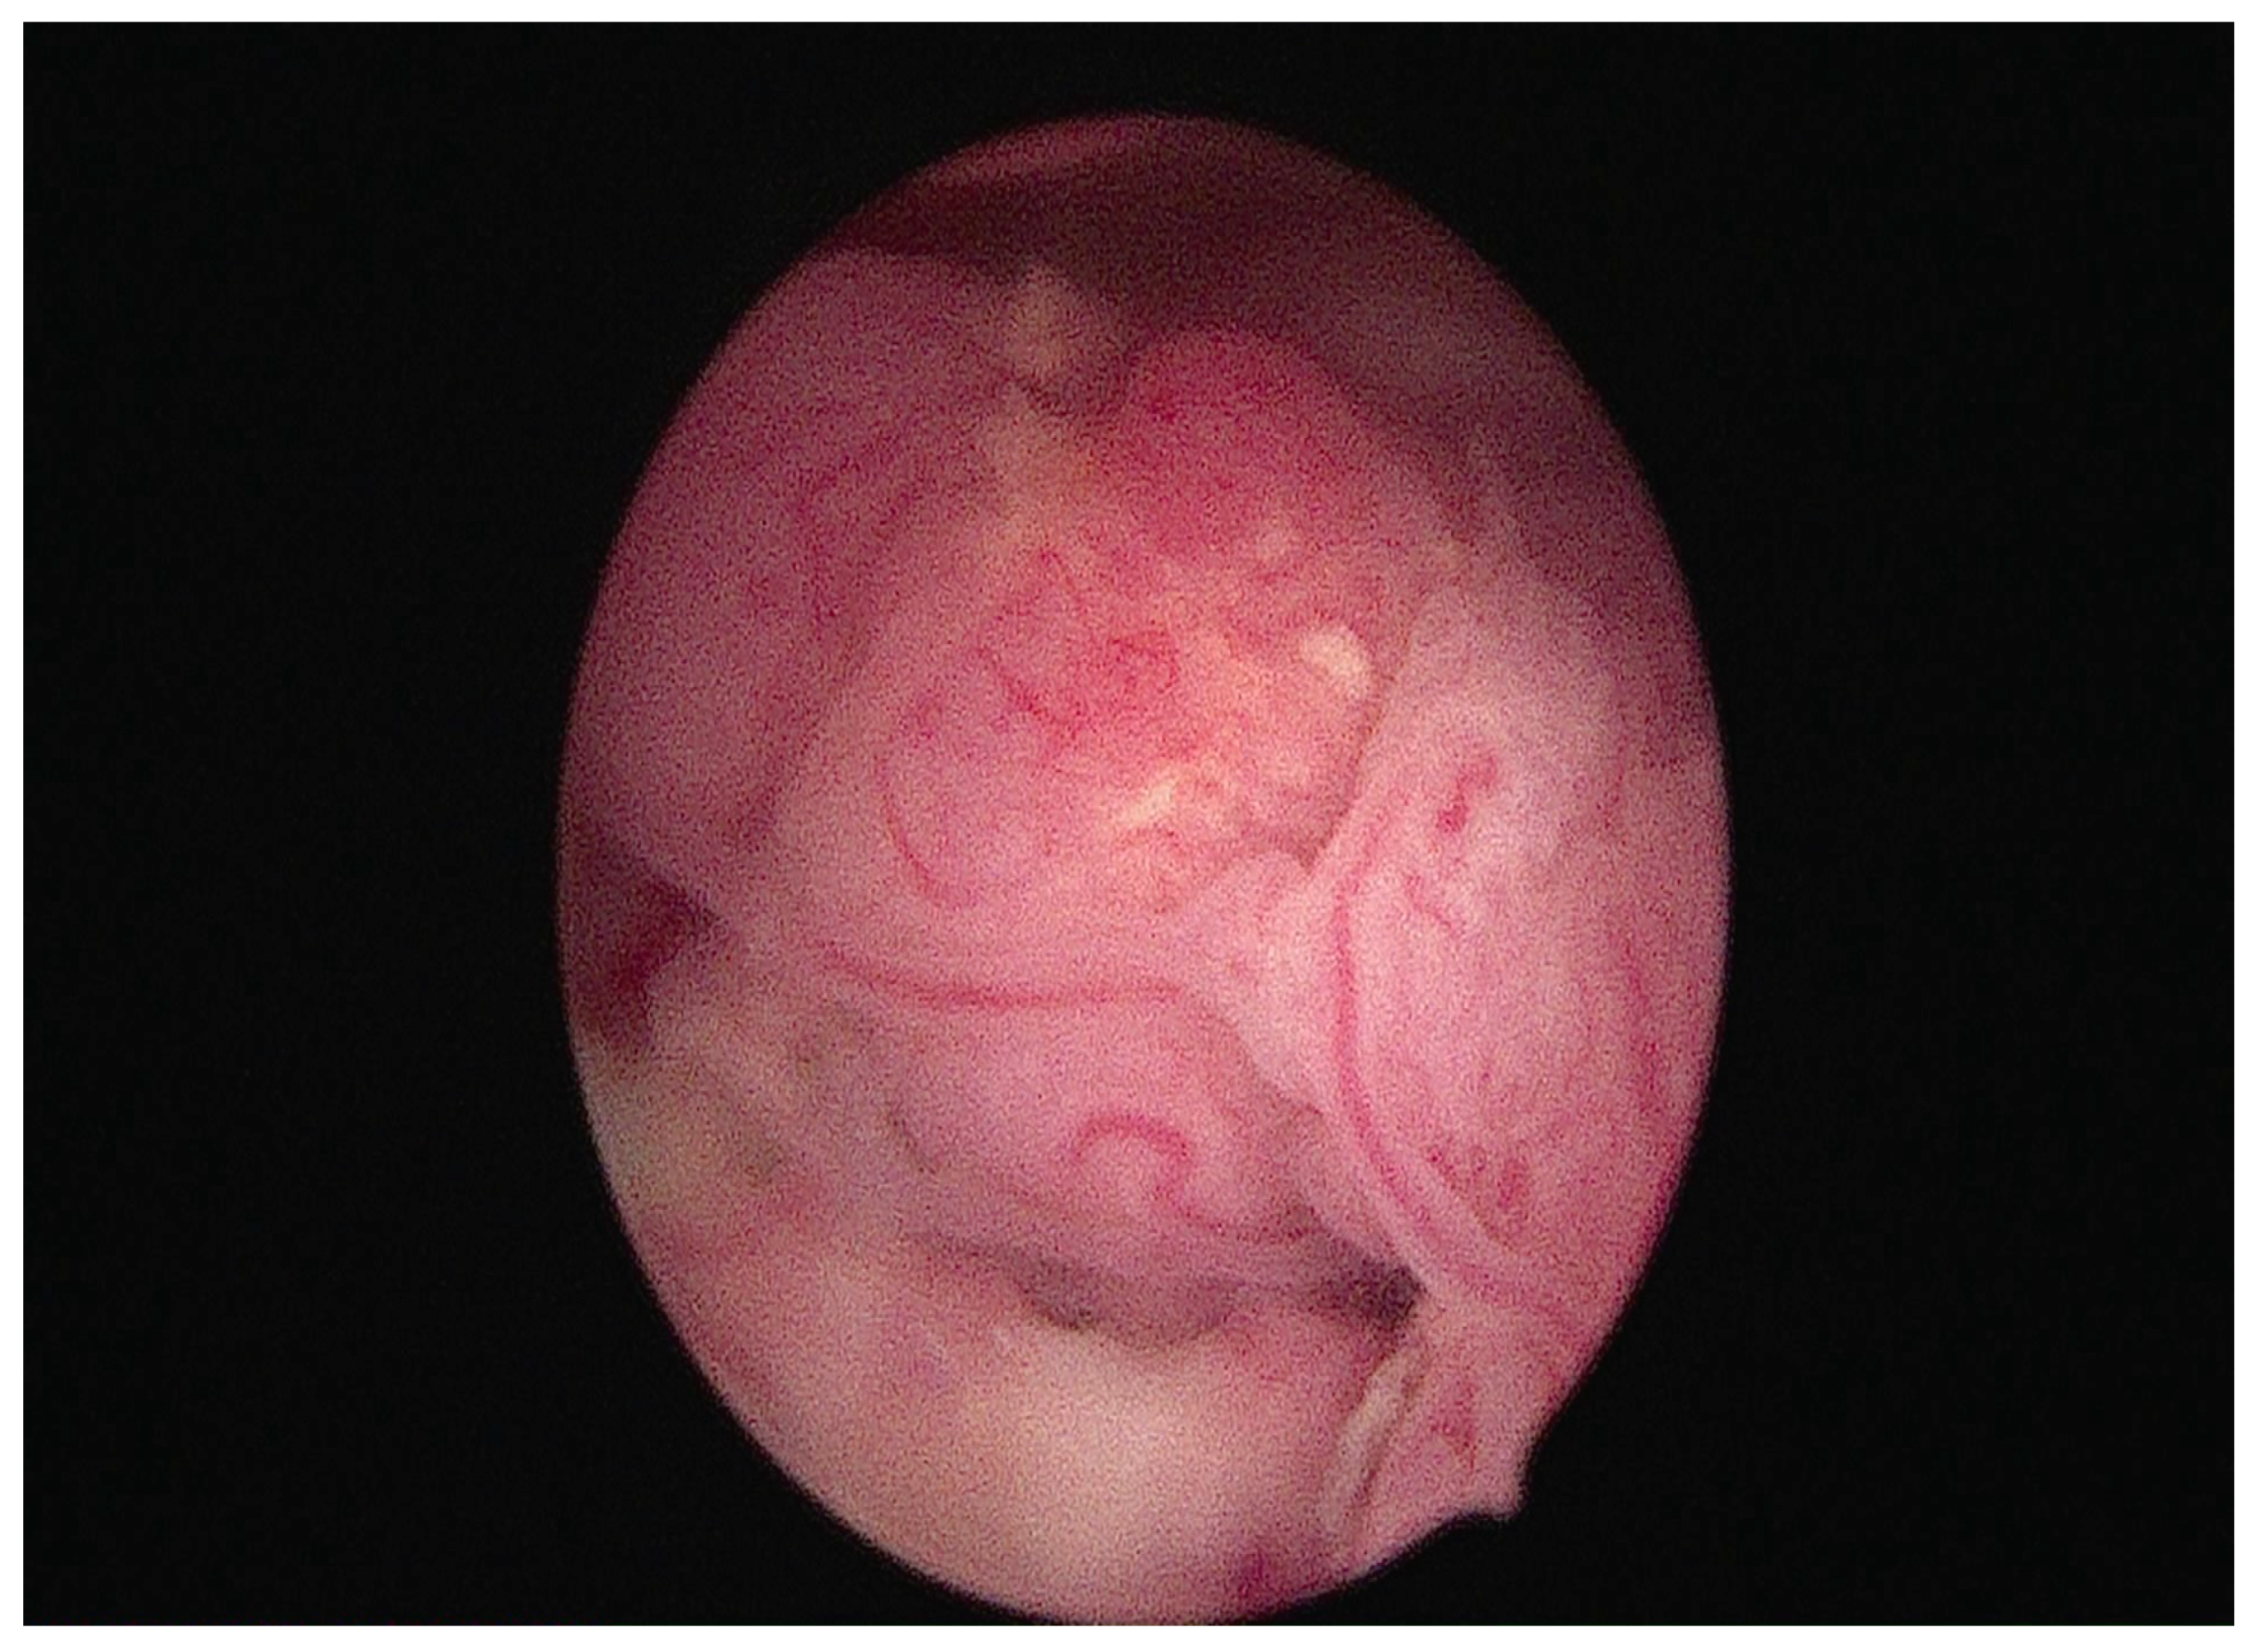

Among the new treatment options, some authors suggest performing an operative hysteroscopy with a pre-treated endometrium resection to promote complete cytoreduction before progestin therapy [16,35,38]. Figure 3 shows a hysteroscopic image of a neoplastic endometrial lesion occupying the uterine cavity, treated with a tissue removal device.

Figure 3.

Hysteroscopic view of endometrial cancer with exophytic growth within the uterine cavity, treated with a tissue removal device.